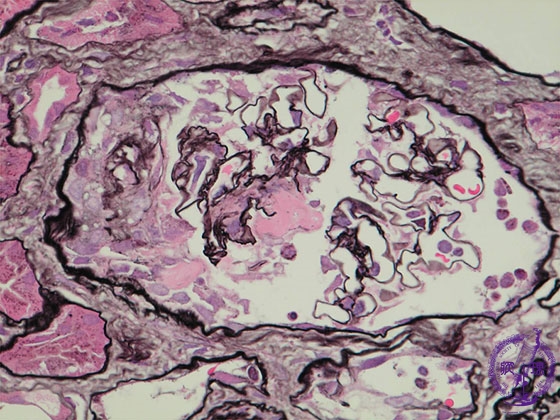

- ★(5)Crescent-forming glomerulonephritis

Microscopic findings ( PAM, high power view):ANCA-related glomerulonephritis. There is disruption of the glomerular loop basement membrane (yellow arrows) as well as fibrin exudates (red dotted line). Bowman’s space contains a cellular crescent (yellow dotted line).